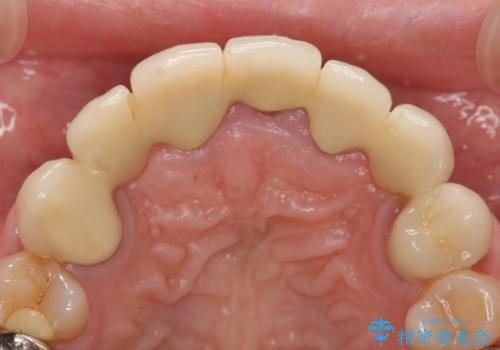

- 昔治療した前歯の被せ物の見た目を改善したいといらっしゃった方の症例です。

左上4番目の歯から右上3番目の歯まで計7歯のクラウンを除去し、オールセラミッククラウンによる補綴を行いました。

今回用いたオールセラミッククラウンはジルコニアフレームという白い素材の上にセラミックを盛っているため、審美性が非常に高いのが特徴です。

また、ジルコニアは人工ダイヤモンドの材料にも使われているほど高い強度を持っており、そのためオールセラミッククラウンは審美性だけでなく、奥歯やブリッジの補綴も可能とするクラウンです。